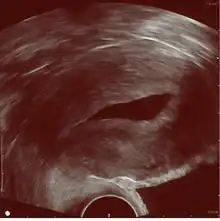

The examination can be performed by transabdominal ultrasonography, generally with a full bladder which acts as an acoustic window to achieve better visualization of pelvis organs, or by transvaginal ultrasonography with a specifically designed vaginal transducer. Transvaginal imaging utilizes a higher frequency imaging, which gives better resolution of the ovaries, uterus and endometrium (the fallopian tubes are generally not seen unless distended), but is limited to depth of image penetration, whereas larger lesions reaching into the abdomen are better seen transabdominally. Having a full bladder for the transabdominal portion of the exam is helpful because sound travels through fluid with less attenuation to better visualize the uterus and ovaries which lies posteriorly to the bladder. The procedure is by definition invasive when performed transvaginally. Scans are performed by health care professionals called sonographers, or gynecologists trained in ultrasound.